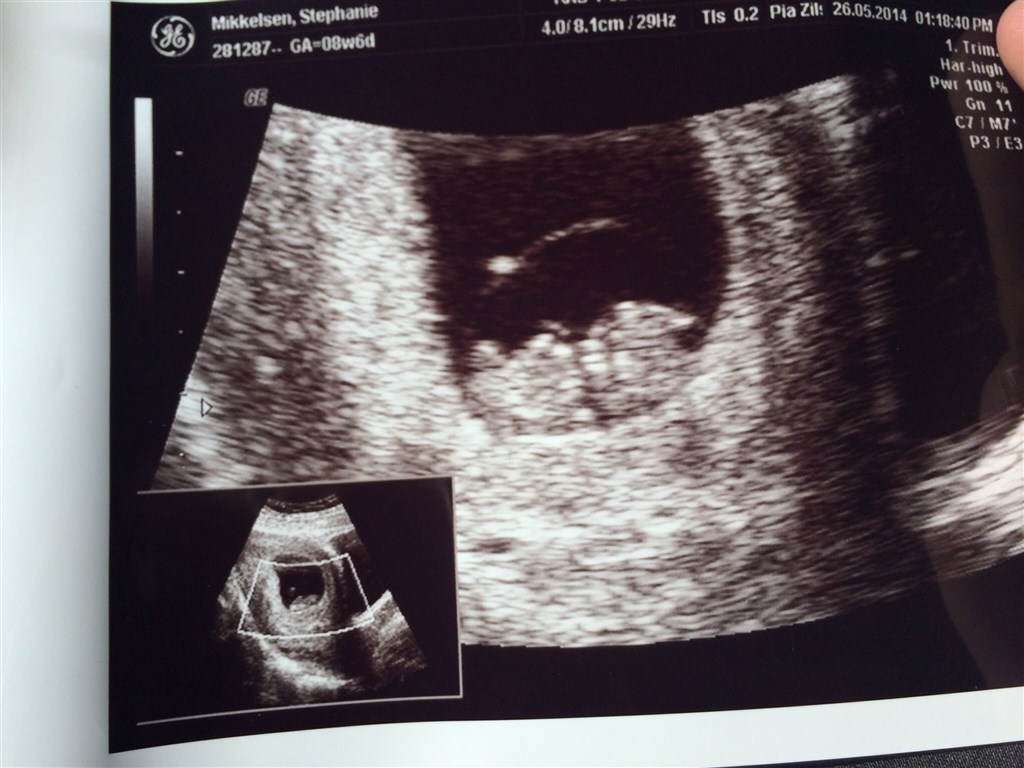

Har dette billede fra 7+5 mener jeg det er. Har fået ny termin efter 3 scanninger,  (1 tryghedsscanning, 2 nf scanninger da jeg ikke alligevel var langt nok henne ved den 1.) så har haft lidt svært ved at holde rede i det.

Og de kan sagtens se hjertet banke

Vedhæftede fotos (klik for at se i fuld størrelse)